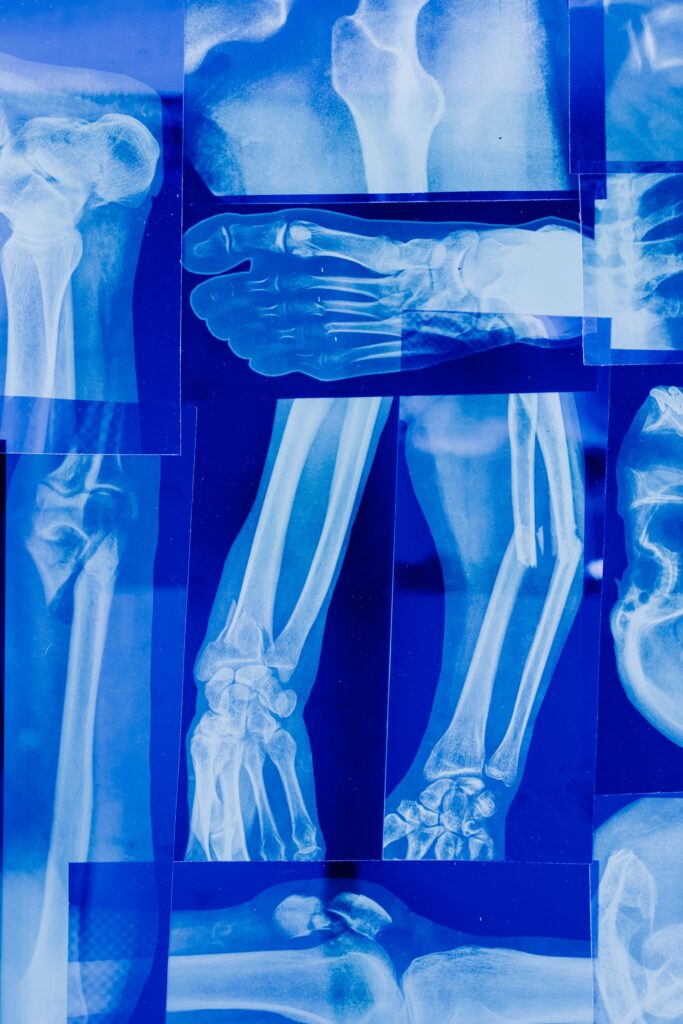

Vivir con dolor en las articulaciones, las rodillas inflamadas y hasta deformes, a tal punto que pueda sufrir inestabilidad, con alta probabilidad de caerse, y limitación para caminar, es mucho más común de lo que se piensa, puesto que la osteoartrosis, enfermedad que causa todos estos síntomas, la padecen por más de 300 millones de personas en todo el mundo, según datos epidemiológicos de la OMS.